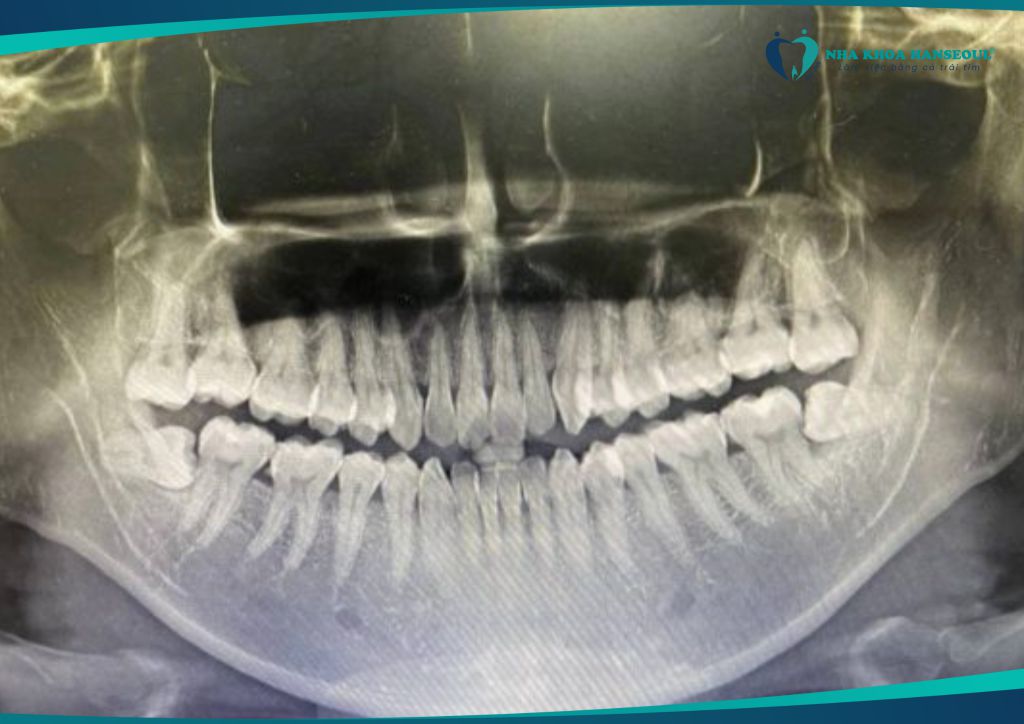

KHÔNG nên trì hoãn nếu:

- Răng đã đau nhiều lần trong năm

- Có dấu hiệu viêm, sưng, chèn ép

- Chụp phim cho thấy mọc lệch, mọc ngầm, đâm vào răng khác

Việc trì hoãn sẽ khiến tình trạng chuyển biến xấu. Việc nhổ răng trở nên phức tạp hơn và ảnh hưởng đến sức khỏe toàn diện.